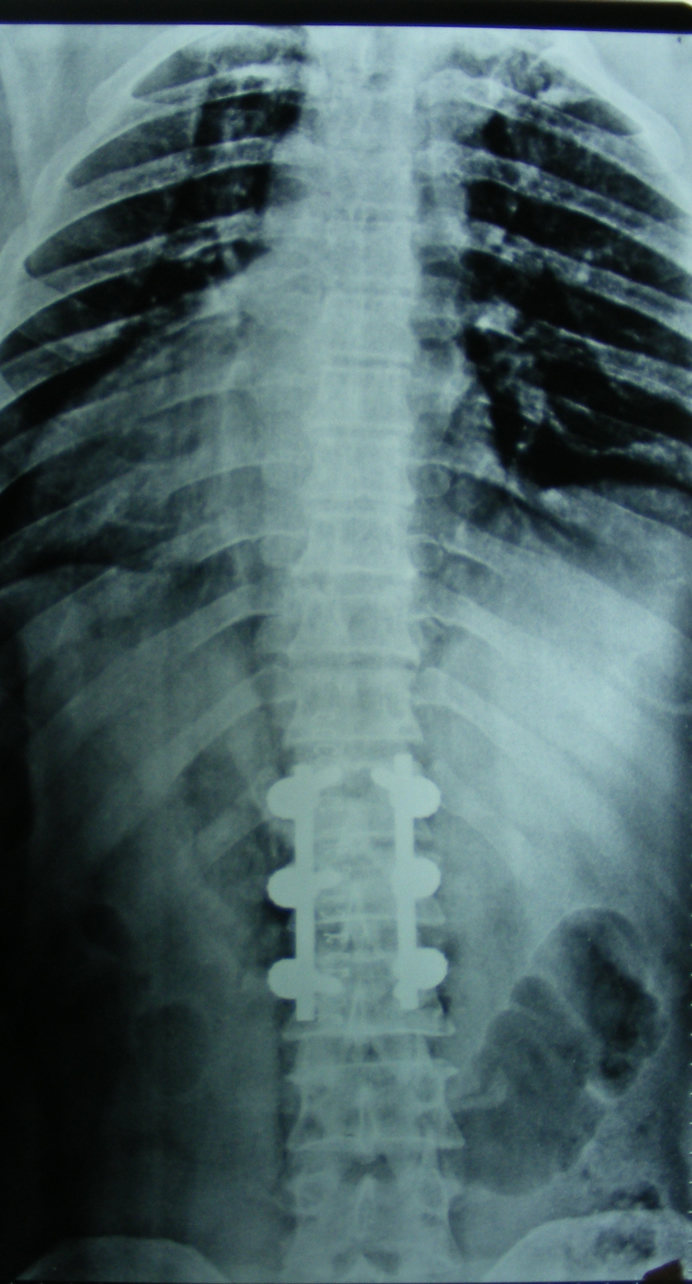

Eğer travma ilerleyen dönemde deformiteye yol açmayacaksa veya sinirlere baskı yaparak nörolojik bulguya neden olmadıysa korse ile tedavi edilebilir. Bu amaçla sert polietilen korseler ya da metalden yapılmış çerçeve tipi korseler kullanılabilir. Omurganın ağır zarar gördüğü durumlarda ileride oluşabilecek deformiteyi engellemek için omurganın vida ve çubuklarla sabitlenmesi gerekebilir. Nörolojik bulgu oluşturan bir kemiksel bası varsa, aynı seansta bu bası da ortadan kaldırılabilir.